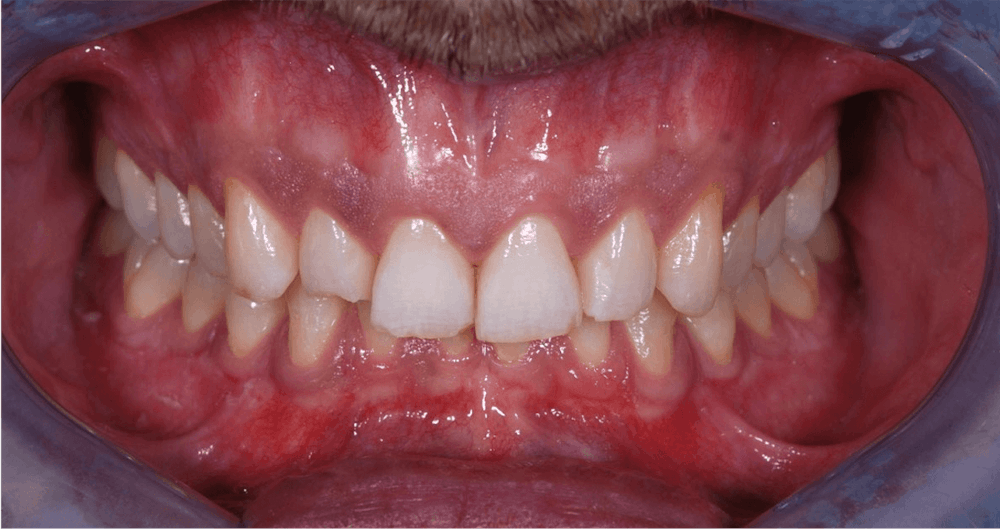

This patient came to see me because he felt his teeth did not show in his smile.

He had a low lip line, some dentoalveolar extrusion of the lower anteriors and a deep bite. His maxilla was retrognathic and he could have had orthognathic surgery to improve the position of his maxilla, but he declined. Instead, we restored his upper 10 teeth with IPS e.max restorations, equilibrated to function. We could not add much length, but we did improve the dominance of his centrals with more space between the line angles creating more reflective surface.

Final result is a more dominant smile for the patient.